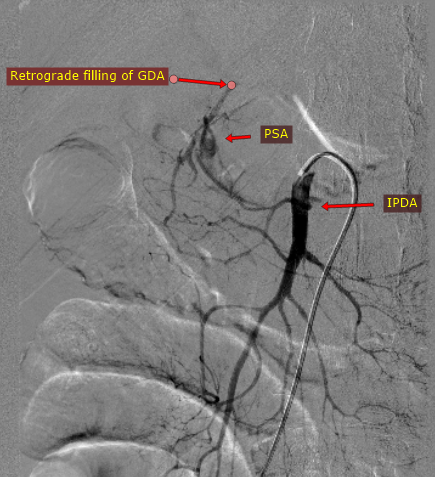

@iRadBIR_Chennai @SRajesh_IR @karananandpara @iRadRock @keithppereira @ChengaziMD @Murthy_CS_ @PulkitRangarh @drochohan I would still trap the aneurysm via SMA. Stenosis is distal to the GDA stump. So it should largely make no difference. It may be vasospasm which may get relieved.

A straightforward GDA Pseudoaneurysm embolization. But Angiogram looks like this, how would you proceed further? #iRad #MedTwitter @SRajesh_IR @karananandpara @iRadRock @keithppereira @ChengaziMD @Murthy_CS_ @lenonjdee @PulkitRangarh @drochohan @ChengaziMD